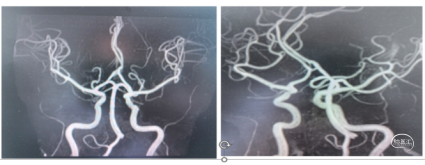

患者男,59岁,右侧肢体活动不灵1小时25分钟。神经系统:神志清楚,反应迟钝,言语基本流利,双侧额纹、鼻唇沟对称,伸舌左偏,四肢肌张力正常,右上肢肌力3级,右下肢肌力2级,右侧巴氏征(+)。NIHSS评分9分。 ASPECTS-CT评分:前循环9分。MRI显示左侧大脑前动脉区域埂塞可能,MRA大脑前动脉A2以远未显影。

造影右侧大脑前动脉缺如(未发育),左侧大脑前A2段闭塞。

大脑前动脉血管较细、路径迂曲,一般抽吸导管到位比较困难,又恐4mm及以上直径的取栓支架用于大脑前动脉对血管损伤较大,遂使用3*20mm小支架联合5F 125中间导管,SWIM取栓。

手术所用耗材:取栓支架 3*20mm、远端通路导管 5F 125cm 、0.014inch 300cm微导丝、2.4F微导管、6F长鞘、0.035in泥鳅导丝、5F造影导管。

1、微导丝越过闭塞处到达A3段。下图1

2、5F 125中间导管辅助高到位下图2。

3、手推造影明确血栓位置下图3。

4、微导管到达A4段下图4。

5、3*20取栓支架到位回撤微导管,多点显影标记,清晰可见支架打开良好下图5。

造影显示血管再通。

术后替罗非班6ml/h 持续泵注24小时桥接双抗治疗,术后使用依达拉奉右崁醇 30mg 2次/日,监测血压维持在收缩压140mmHg左右。

术后14天,神经系统:神志清楚,高级智能检查正常,言语基本流利,

双侧额纹、鼻唇沟对称,伸舌左偏,四肢肌张力正常,右上肢肌力4级,

右下肢肌力3级,右侧巴氏征(+)。NIHSS评分:3分。